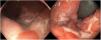

Nine patients with anorectal involvement underwent rectosigmoidoscopy, which revealed extensive superficial ulcers with geographic borders in the anal canal and rectal ampulla (Fig. 4). The main histopathology findings were granulomatous patterns with nonspecific chronic infiltrates associated with acute cryptitis in 3 cases (Fig. 5). No microorganisms were observed in the biopsy, and immunohistochemistry for cytomegalovirus and Treponema pallidum was negative. Patient 1 underwent magnetic resonance imaging, which revealed edema of the rectal mucosa with obliteration of the lumen extending into the mesorectal fat associated with multiple enlarged pararectal and hypogastric lymph nodes. In patients with classic LGV, ultrasound proved useful for demonstration and follow-up of the enlarged inguinal lymph nodes, abscesses, and fistulas. Serovar L2 of C trachomatis (GenBank reference CP002682.1) was identified as the etiologic agent in all cases.